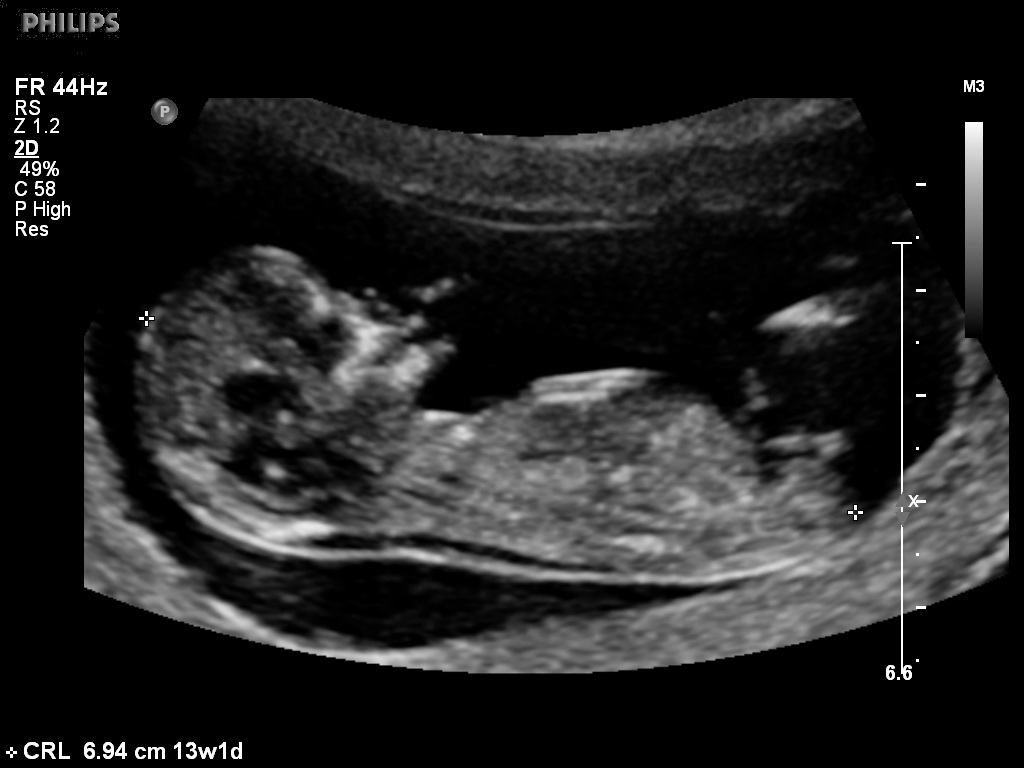

Attachment 5246Attachment 5247

HI i had my scan done at 12 weeks and 1 day(very accurate as i had previous scans) but this bub must of had a growth spurt as it measured 13 weeks on the day. Any ideas of the gender? Would it be more accurate as bub measured 13 weeks?? thanks!!